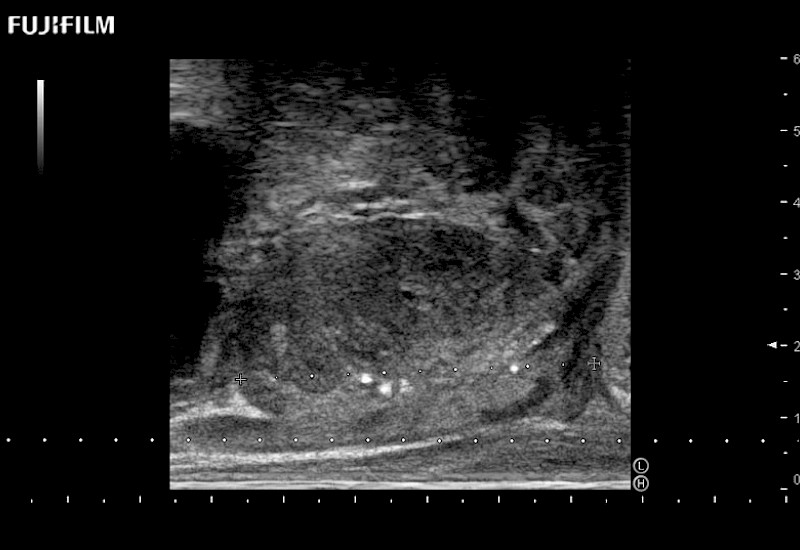

Ideal transducer for Transperineal Biopsy, Hydrogel Spacer Placement, Brachy LDR & HDR, Cryo, and MPMRI procedures.

Main Specifications: